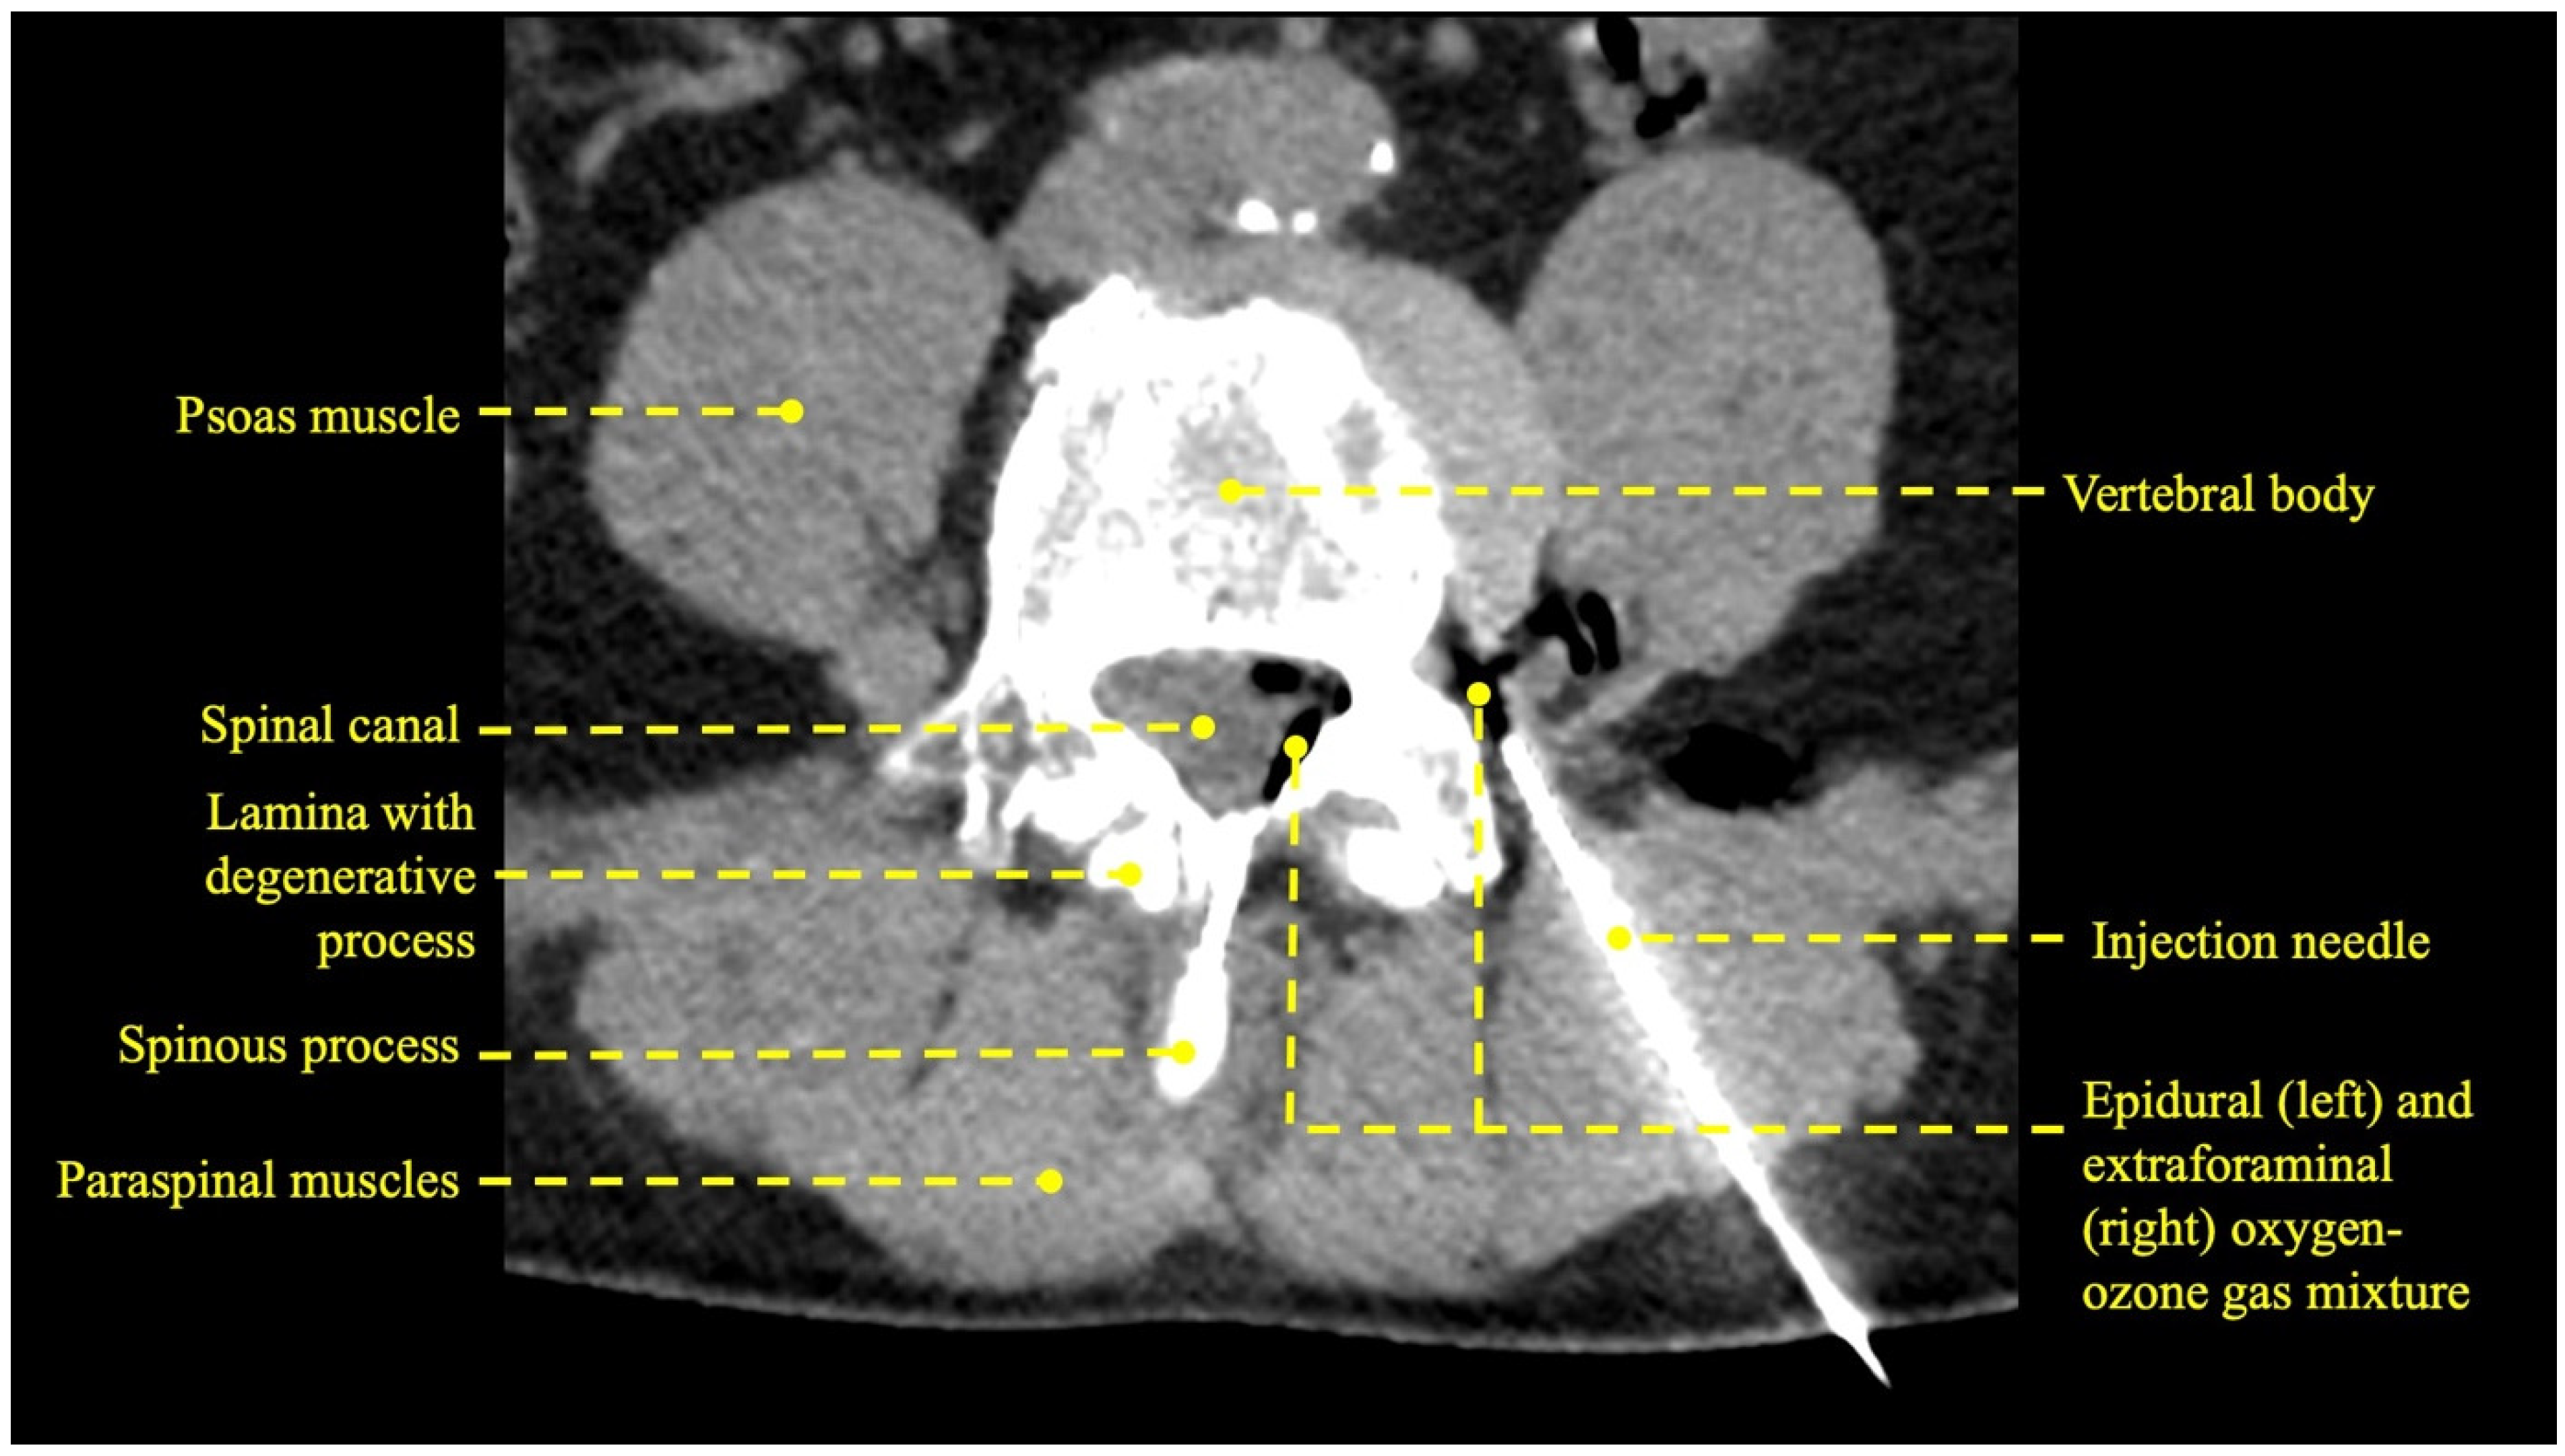

3.1. Procedural Technical Outcome

- Muto, M.; Andreula, C.; Leonardi, M. Treatment of herniated lumbar disc by intradiscal and intraforaminal oxygen-ozone (O2-O3) injection. J. Neuroradiol. 2004, 31, 183–189. [Google Scholar] [CrossRef] [PubMed]

- Giurazza, F.; Guarnieri, G.; Murphy, K.J.; Muto, M. Intradiscal O2O3: Rationale, Injection Technique, Short- and Long-term Outcomes for the Treatment of Low Back Pain Due to Disc Herniation. Can. Assoc. Radiol. J. 2017, 68, 171–177. [Google Scholar] [CrossRef]